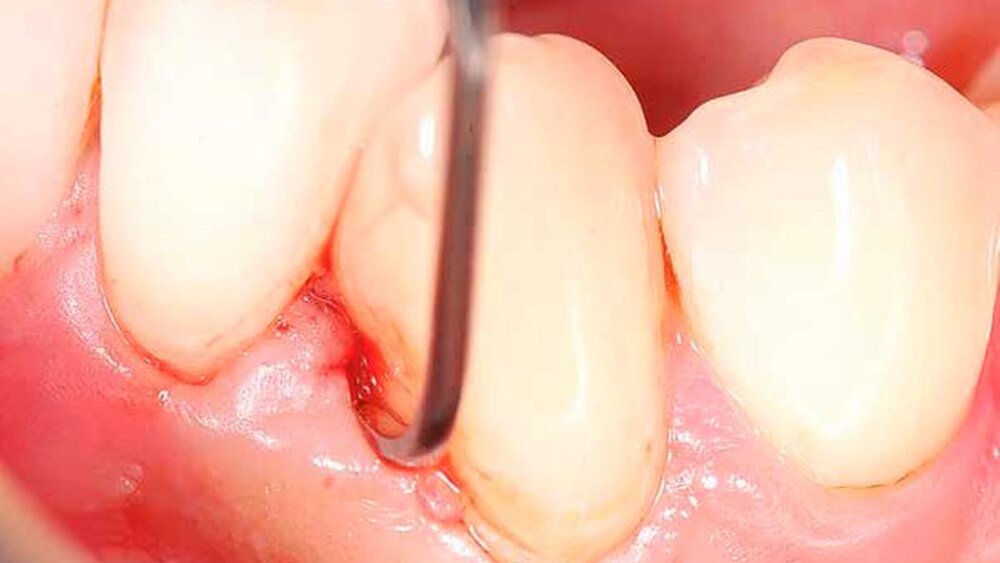

Reduktion der Sondierungstiefen (st) und Attachmentgewinne sechs und zwölf Monate nach nichtchirurgischer Therapie

Von großem Interesse sind derzeit weiterhin subgingival eingesetzte Pulver-Wasserstrahl-Geräte. Mit gering abrasivem Pulver, häufig auf Glycin-Basis, können damit schnell und gründlich Biofilme, aber keine mineralisierten Ablagerungen entfernt werden [Flemmig et al., 2012]. Das Verfahren hat daher seine Stärke im Bereich der unterstützenden Parodontitistherapie, wo in der Regel keine ausgeprägten Konkremente zu erwarten sind. Für einen denkbaren Einsatz während der subgingivalen Instrumentierung liegen noch keine ausreichenden klinischen Daten vor, insbesondere ist wahrscheinlich die dem Verfahren immanente Gefahr eines Luftemphysems bei dem in der ersten Behandlungsphase oft noch stark aufgelockerten Gewebe (vgl. Abbildung 1) noch deutlich erhöht.